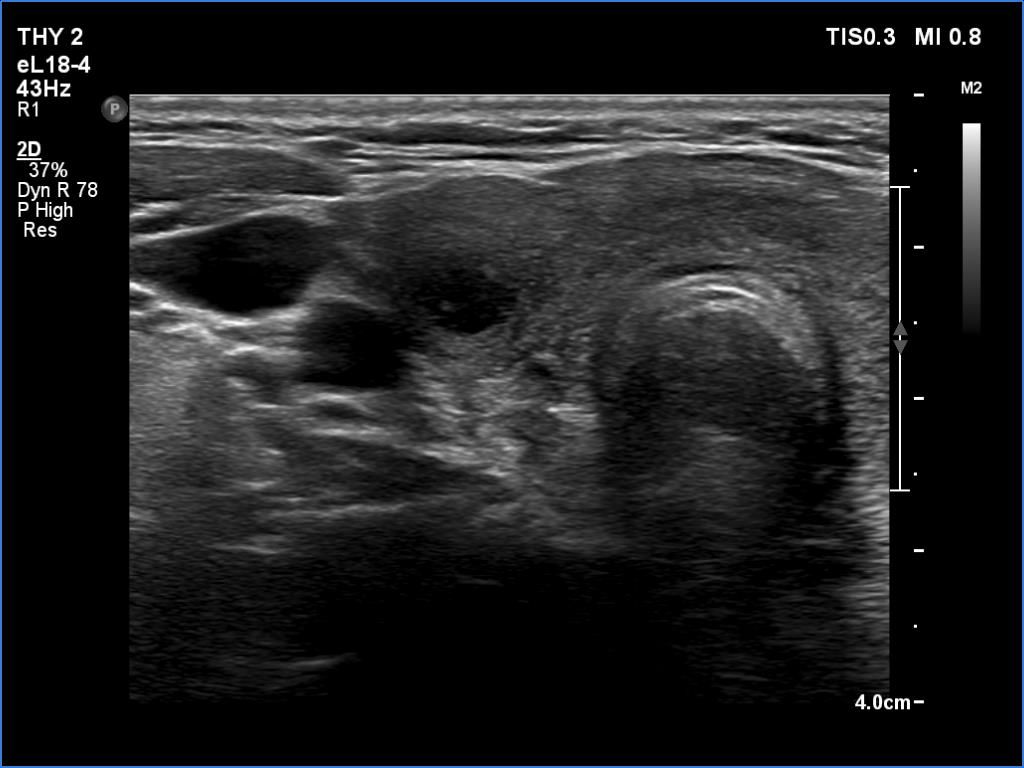

Right lobe, longitudinal scan

Right lobe, another transverse view. There is a deeply hypoechoic or cystic lesion.